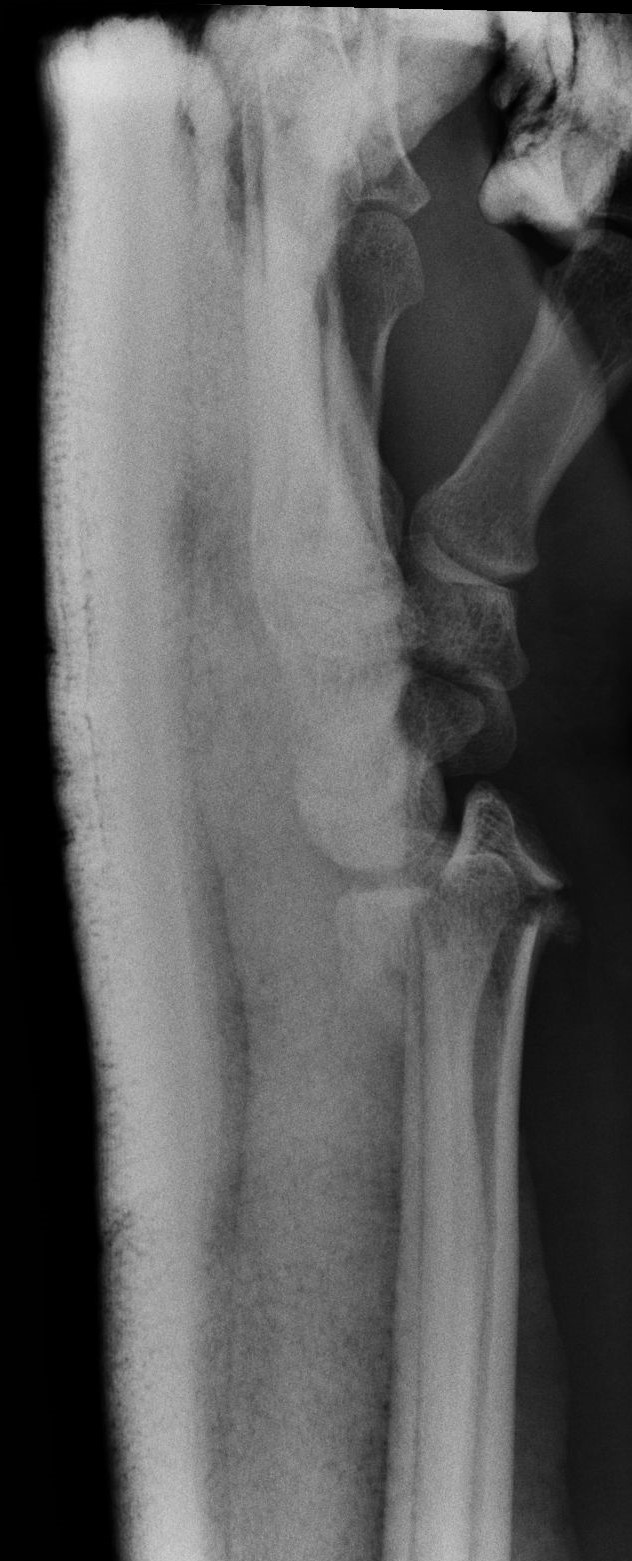

Successful surgery to reduce and fixate with the plate of neglected, displaced fracture of the distal radius

Treatment of neglected, displaced or united distal radial fractures (DRFs) is difficult, because it requires either wedging the almost consolidated fracture and reduction to the correct position, or cutting the united bone and putting it in the correct position (corrective osteotomy). Both treatments are associated with the risk of failure and complications. The paper presents a case of almost fully united DRF in a man, in whom 5 weeks after the injury, and after unsuccessful primary fixation with K-wires, the bone fragments were surgically wedged, aligned and fixed with a palmar plate. The result of treatment after 2 months was satisfactory. Early surgery allowed for a significant shortening of the recovery period and allowed the patient to return to work.